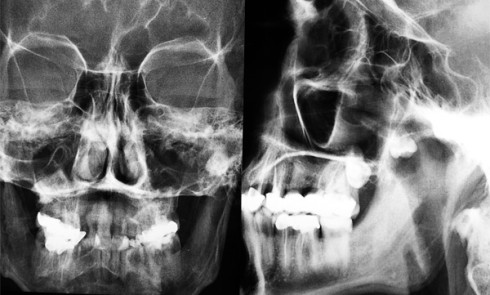

1. Quelles sont les propositions exactes au vu du panoramique et des clichés de face et de profil (fig. 1a...